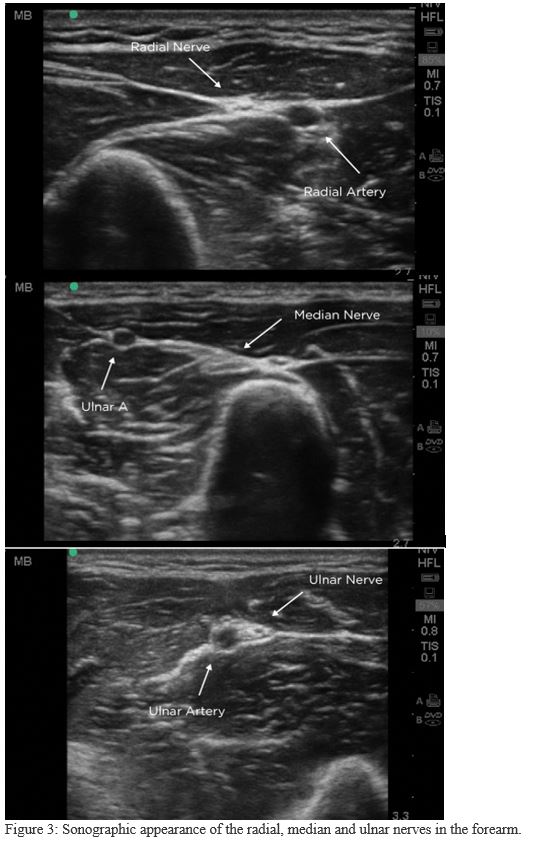

3. Locate the nerves (Figure 3)

Difficulty clearly identifying nerves amongst the other structures is a common frustration. In cross-section on US, a nerve appears as an elliptical bundle containing many small scattered echogenic foci and running within a fascial plane. These blocks are best performed in the mid-forearm. The distal forearm has many tendons which may be mistaken for nerves and in the proximal forearm the nerves are deeper making them more difficult to target.

Finding the radial nerve:

- Find the radial artery in cross section at the wrist.

- The radial nerve is seen adjacent to the artery on the radial side.

Finding the median nerve:

- Start with probe centered on volar wrist and move proximally to mid-forearm.

- The median nerve can be visualized between flexor digitorum muscles.

Finding the ulnar nerve:

- Find the ulnar artery in cross section at the wrist.

- The ulnar nerve is seen adjacent to the artery on the ulnar side.